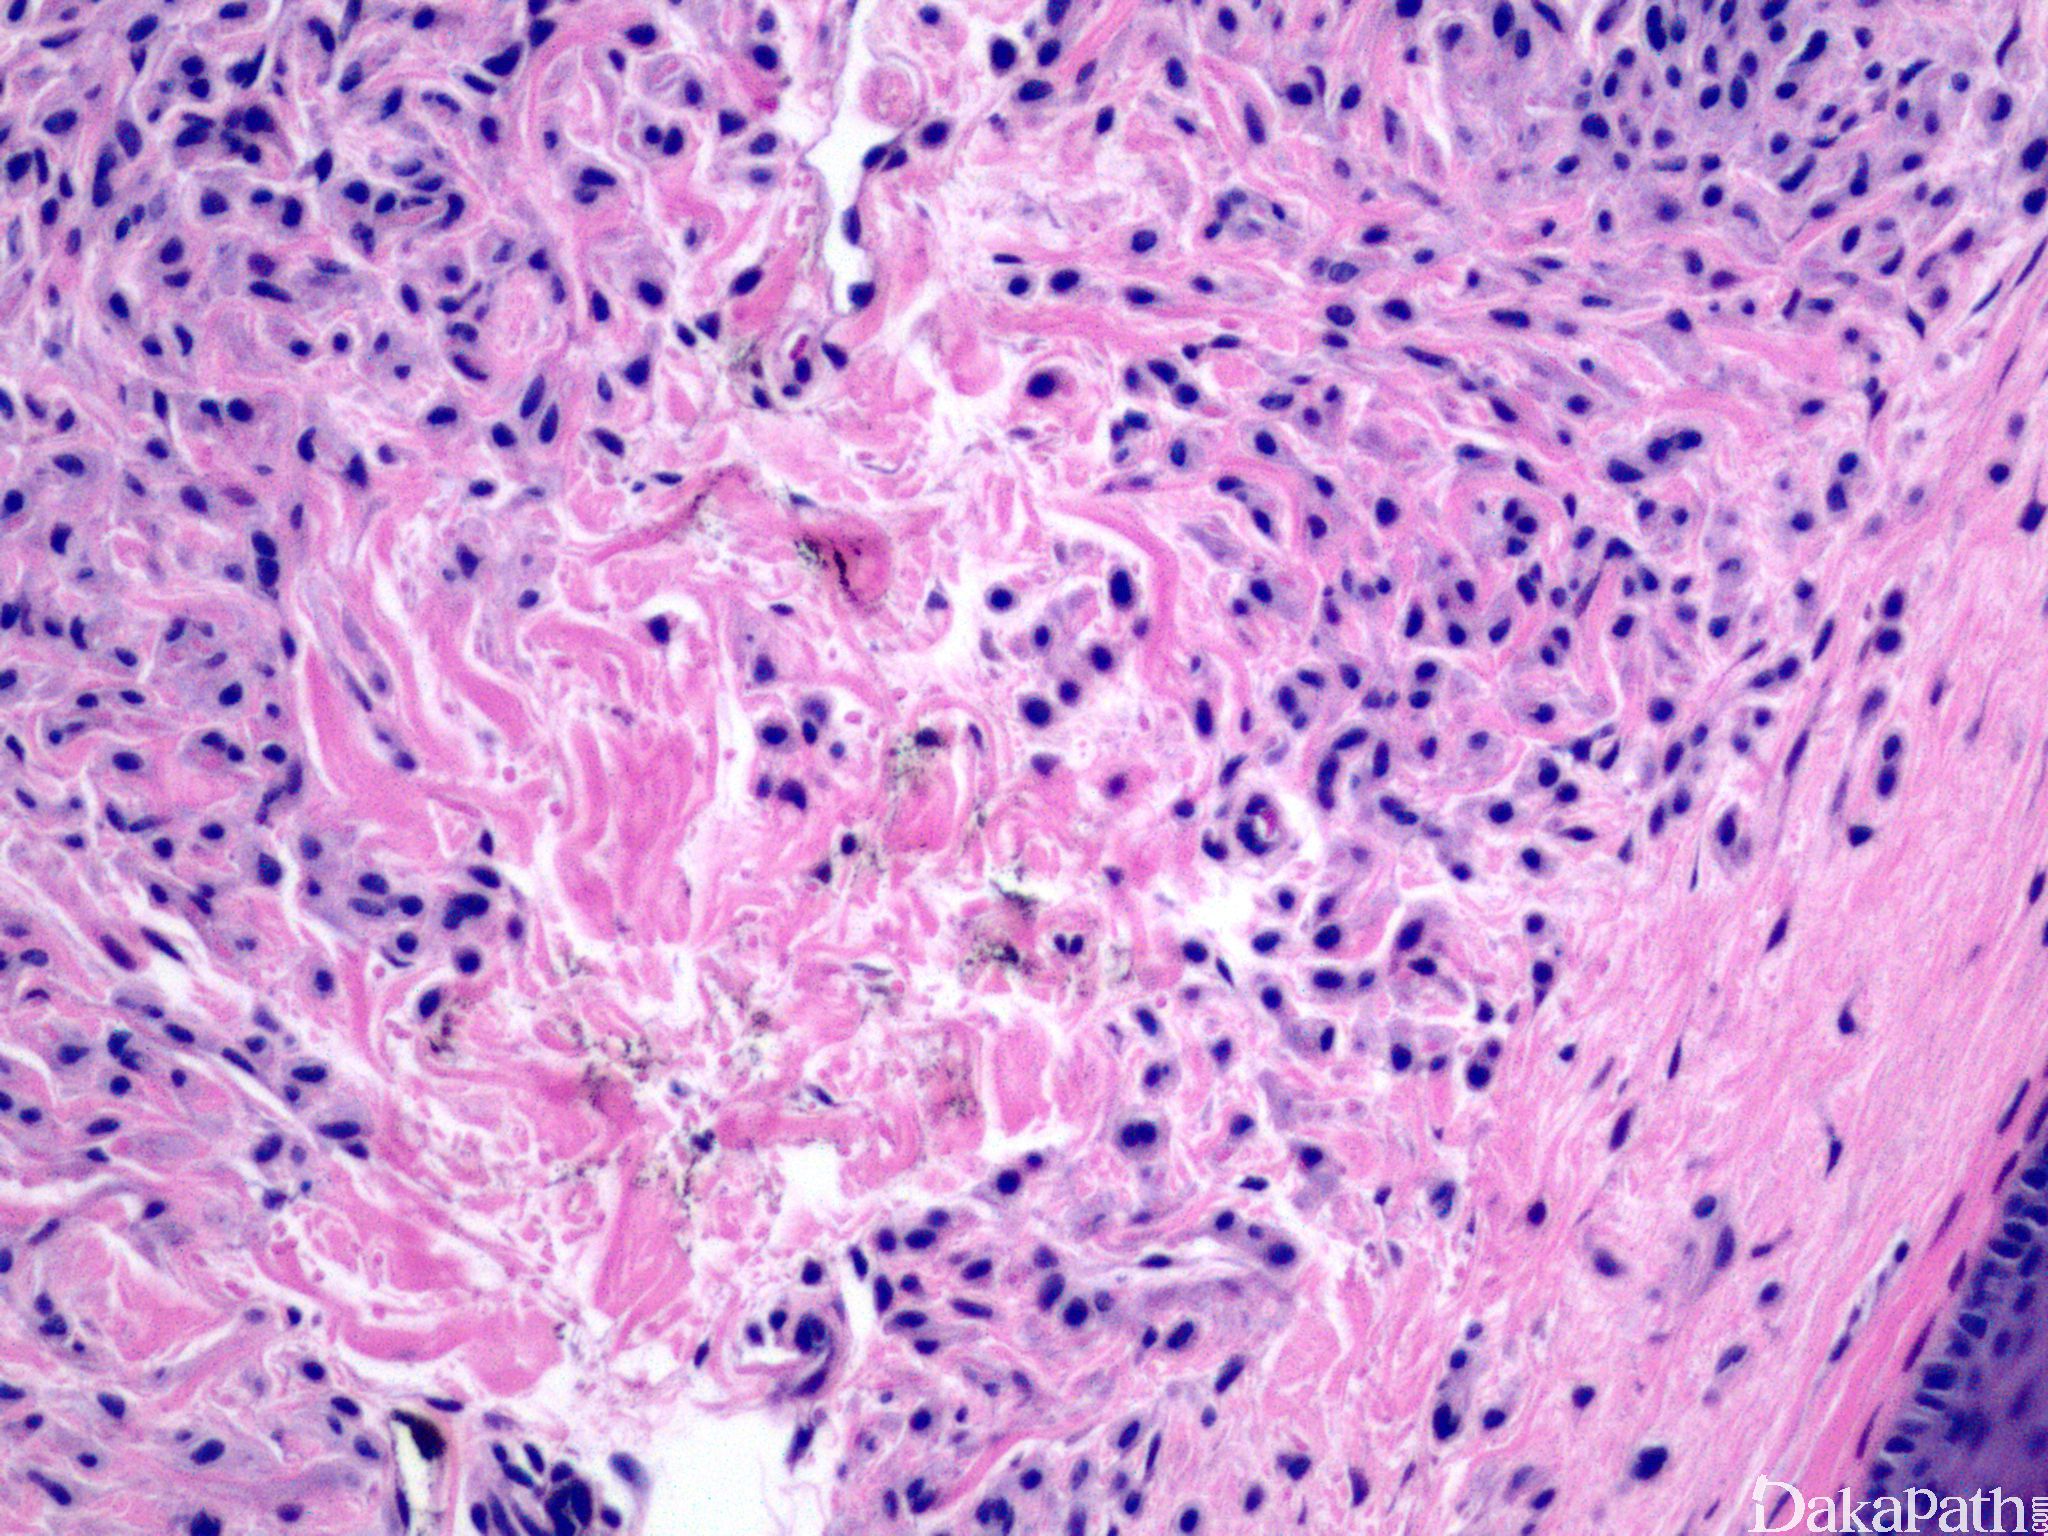

同时具有交界痣和皮内痣两种形态特征。

同时具有交界痣和皮内痣两种形态;

交界痣成分类似于交界痣,无 Paget 样扩张,对称性生长,无细胞异型性及核分裂像,随着年龄增加,交界痣成分逐步较少;

皮内痣成分包括巢状或线性排列的痣细胞,细胞小,浆少,核规则,从浅表到基底有逐步成熟现象,细胞逐渐变细或呈梭形,色素减少;

真皮内细胞巢被纤维组织分隔;

基底常见成簇淋巴细胞浸润;

个别病例伴黏液变性;

偶尔可见核分裂像,无病理性核分裂像。